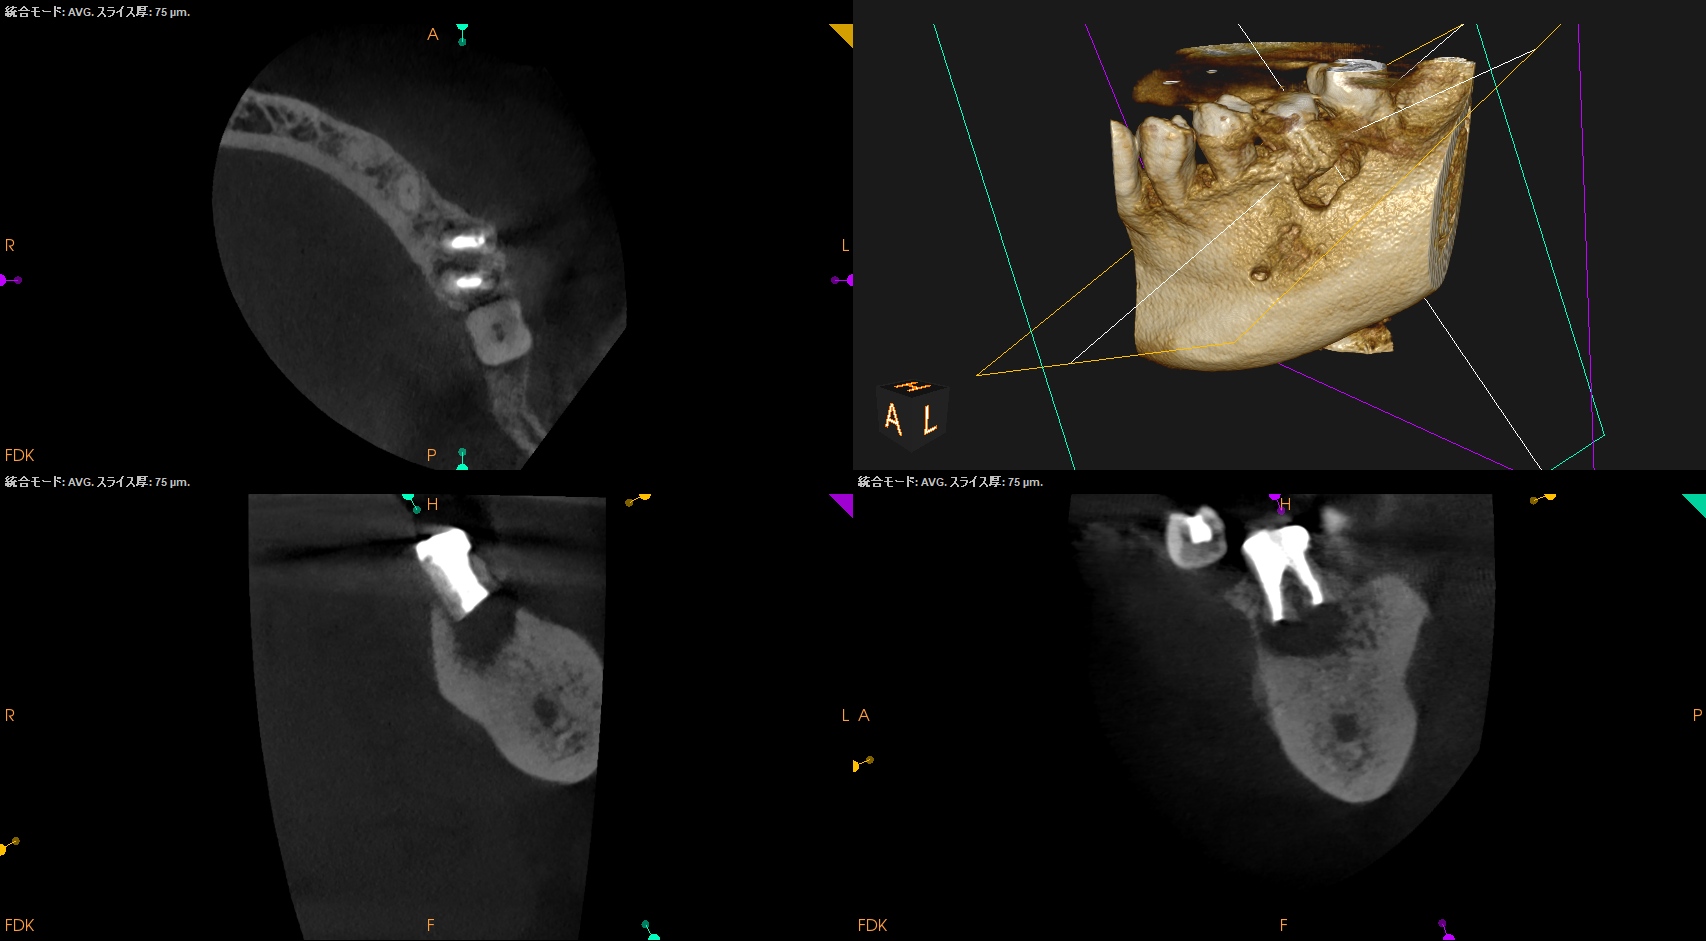

術後にPA, CBCTを撮影した。

M

D

問題はないだろう。

以下のようにPA,CBCTはなった。